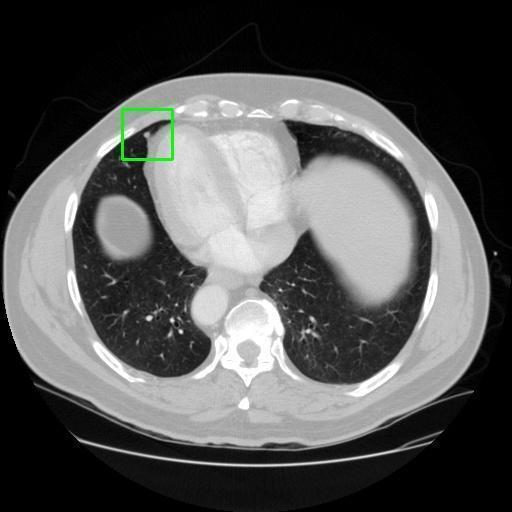

We developed an AI-based system using deep learning models for analyzing lung CT scans to detect and classify pulmonary nodules. We chose the YOLOv11 architecture for its enhanced object detection capability and adapted it specifically for medical imaging, incorporating pixel-level precision and severity classification.

Classification into three severity levels with colored bounding boxes.

Successfully built and deployed an AI model (YOLOv11) capable of detecting lung nodules in CT scans with high accuracy and real-time performance.

Designed a severity classification system that categorizes nodules into null, moderate, and severe using colored bounding boxes, assisting in rapid clinical decision-making.